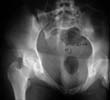

Preop Inlet

Preop Outlet